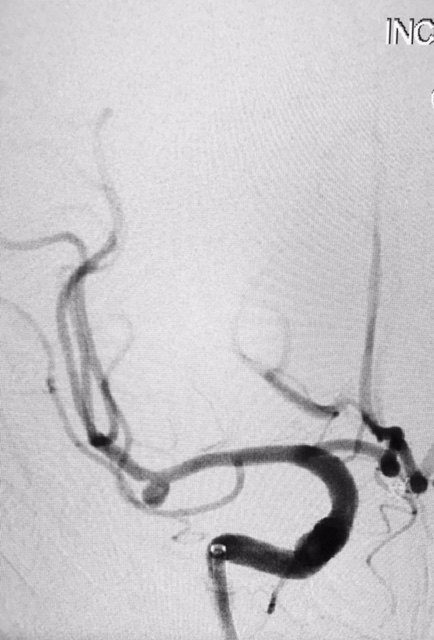

Tratamento de aneurisma cerebral com auxílio de balão duplo lumém e neurostent LEO